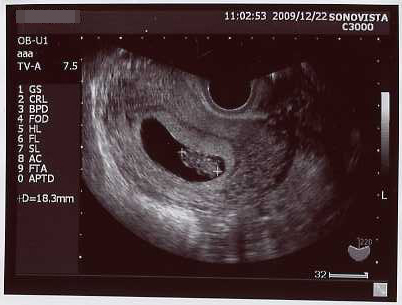

今日は検診でしたー

前回の倍の3.6センチに成長。

なんか劇的にでかくなった気がする!子宮の中いっぱいになってきたw

クリックで拡大。

今までのエコーも並べてみた →エコー写真

前回は、粘土の固まりにポコポコ手足をくっつけたみたいな形だったのが、

今回、首のくびれが出来、手足も伸びて、お人形さんみたいだった!

イヤーンて、寝返り打ちたいような感じで動いた姿が見れたのが嬉しかった。

こんなちっちゃい内から、胎動してるんだね~

心音も聞かせて貰った、今の心拍はオトナの倍位の速さだそうです(*´ω`)